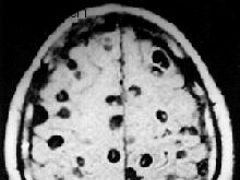

(11)血管性痴呆:多發性腔隙性腦梗死所致的多發性梗死痴呆(MID)是血管性痴呆中常見類型。有老年者屍檢證實,梗死數目越多,痴呆的發生率越高。臨床特徵包括:①有高血壓病、糖尿病、腦動脈硬化等病史;②多數有腦卒中病史;③可查及局灶性和瀰漫性神經功能受損的體徵;④存在不同程度的智慧型障礙、記憶力、計算力、定向力障礙,多數病人情感淡漠,缺乏機敏性,但人格相對保存;⑤CT 或MRI 顯示大腦深部多發腔梗。

(12)無症狀腔隙梗死:患者頭顱CT 或MRI 掃描提示腔隙性腦梗死,但臨床上無明顯定位性體徵和症狀。其梗死部位多見於基底節區、內囊區、放射冠,病灶較小,直徑小於1.5cm。有部分病變則因其產生的神經功能受損的症狀和體徵易於被人忽視或缺乏認識而歸入此類(例如右側額頂區梗死導致體象障礙、病覺缺失或偏側忽視,枕葉梗死導致偏盲或象限盲等)。

(3)多發性梗死痴呆的CT 掃描徵象:①腦皮質或皮質下多發的大小不一的低密度梗死灶,主要分布於基底節區及額、顳、枕葉皮質區。②大部分病例可呈腦萎縮改變,即腦室或腦溝擴大,腦皮質、髓質萎縮。③可伴有Binswanger 病(皮質下動脈硬化性白質腦病,SAE)CT 影像特徵:腦室周圍及半卵圓中心白質內的大致對稱性低密度影,呈月暈狀或傘狀,邊緣模糊,多位於側腦室前方或後方。灰/白質密度比值增加。

6.磁共振(MRI) MRI 對腔隙性腦梗死的檢出率明顯優於頭顱CT 掃描,尤其對腦幹及小腦內的腔梗病灶。病後72h,75%患者的MRI 可顯示≤15mm 的腔隙性病灶,5 天內其檢出陽性率可達92%。急性期腔梗病灶在MRI 的影像特點為T1信號減低、T2 信號增高,其中以T2 信號增高改變更為敏感。